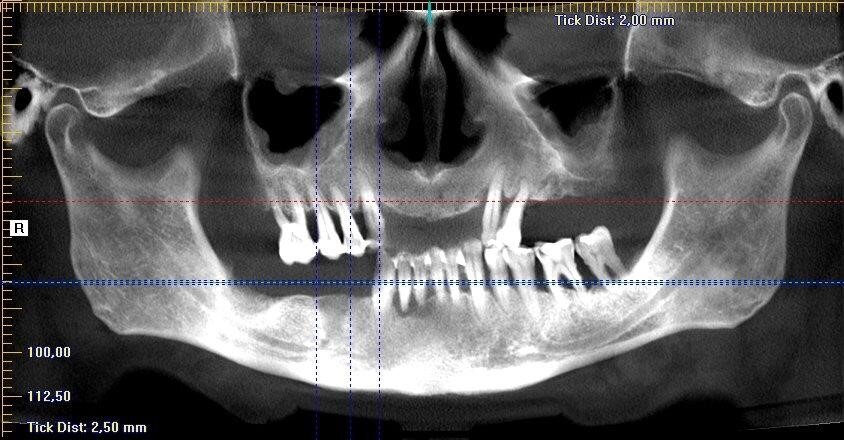

Wykonano CBCT, z którego wynikało, iż pacjent ma chorobę przyzębia. Zakwalifikowano wszystkie 10 zębów żuchwy do ekstrakcji. Zaplanowano zaopatrzenie pacjenta 8 implantami ICX oraz 5 implantami tymczasowymi Alpha Bio w celu wykonania pracy protetycznej tymczasowej bez obciążenia implantów docelowych ze względu na brak kontroli nad pacjentem w okresie wgajania implantów (zdjęcie CBCT oraz wewnątrzustne pacjenta). Za pomocą komputerowego systemu nawigacyjnego 3D został zaprojektowany szablon przytwierdzany 3 pinami do kości żuchwy w celu jego stabilizacji.